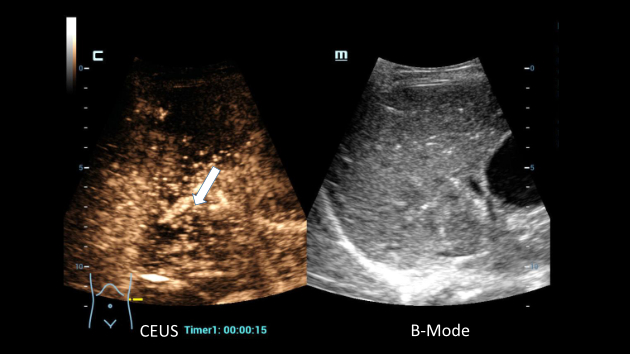

The superior spatial resolution attained with HiFR CEUS provides excellent delineation of the borders of this small gallbladder lesion.